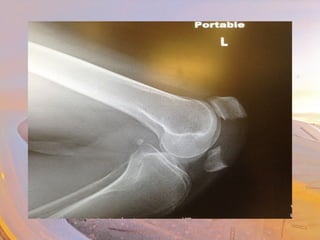

• Cartilage

• Hyaline

• Fibrocartilage

• Meniscus

• Medial & lateral

• Ligaments

• Medial collateral

• Lateral collateral

• Anterior cruciate

• Posterior cruciate

• Patellar

“Unhappy trio”

• Medial meniscus & ligament attached

• Tibia & fibula

• Medial & lateral condyles

• Head of fibula

• Tibial tuberosity